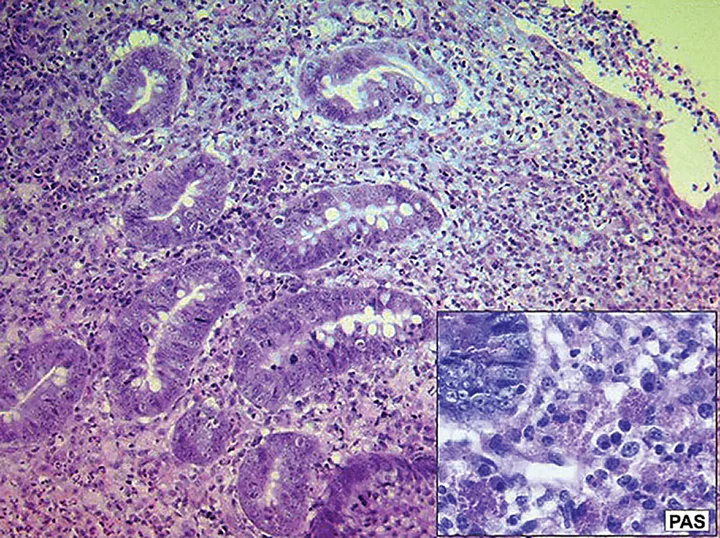

FIGURE 1

Histopathology and Periodic Acid-Schiff (PAS) stain of a sample obtained from a dog with histiocytic ulcerative colitis

Enrofloxacin represents a unique collective effort of the veterinary profession to successfully identify a specific therapy targeting a defined condition (ie, histiocytic ulcerative colitis [HUC; Figure 1] in boxers) that previously had been almost always terminal. This accomplishment serves as an example of the effort that should inform all areas of antibiotic use in small animal medicine,3-6 particularly because of the therapeutic difficulties now presented by antibiotic resistance. Before enrofloxacin was identified as an effective treatment for HUC, most boxers with this disease were euthanized because immunosuppressive therapy was unable to slow the rapid progression of the condition. Invasive E coli was identified as the causal agent, and remission was correlated with eradication of intramucosal E coli organisms following treatment with enrofloxacin (5-10 mg/kg PO q24h for 6-8 weeks).7-9 Cases of HUC in which enrofloxacin was a critical component of successful therapy have also been reported in French bulldogs, an English bulldog, and several other nonboxer breeds.10-12 It is crucial to note that treating dogs with enrofloxacin before obtaining a definitive diagnosis of HUC has been associated with antimicrobial resistance and a poor clinical outcome.13